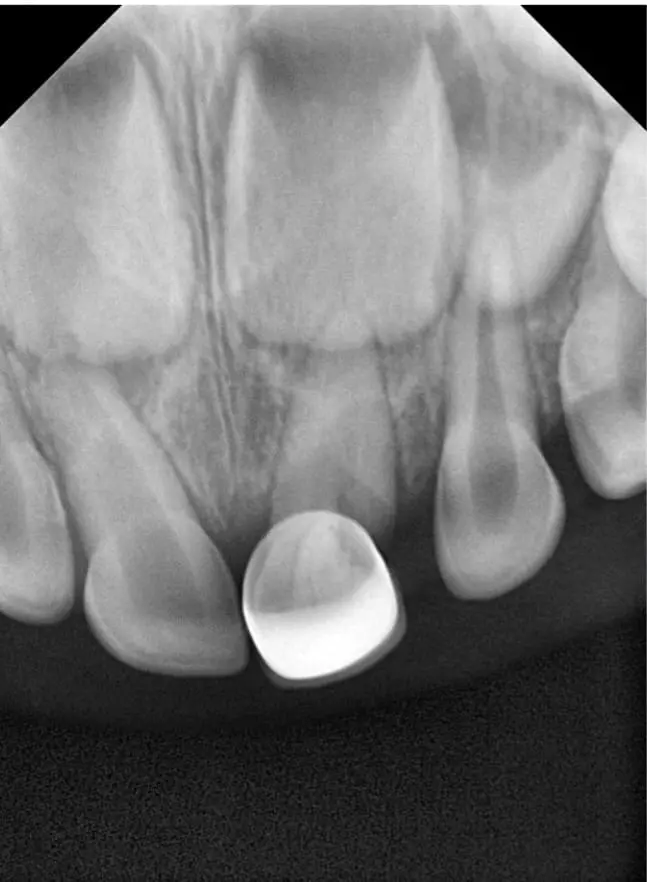

Травма - те, що може статися з будь ким і в будь який момент. А особливо це стосується дітей, які починають активно освоювати навколишнє середовище. Тому знати і вміти зреагувати на травму тимчасового зуба є стратегічно важливим для дитячого стоматолога.

Нерідко, на жаль, трапляються ситуації, коли діти травмують тимчасові зуби. В такому випадку часу на роздуми, як правило, не так багато. Рішення потрібно приймати швидко, часу на підготовку, як правило немає. Саме тому дитячому стоматологу потрібно розуміти, що потрібно робити, а що робити не потрібно. Травми коронкової частини і кореня, навколишніх тканин - що, як і коли робити? В якому випадку терміново втручатись, як коли спостерігати.